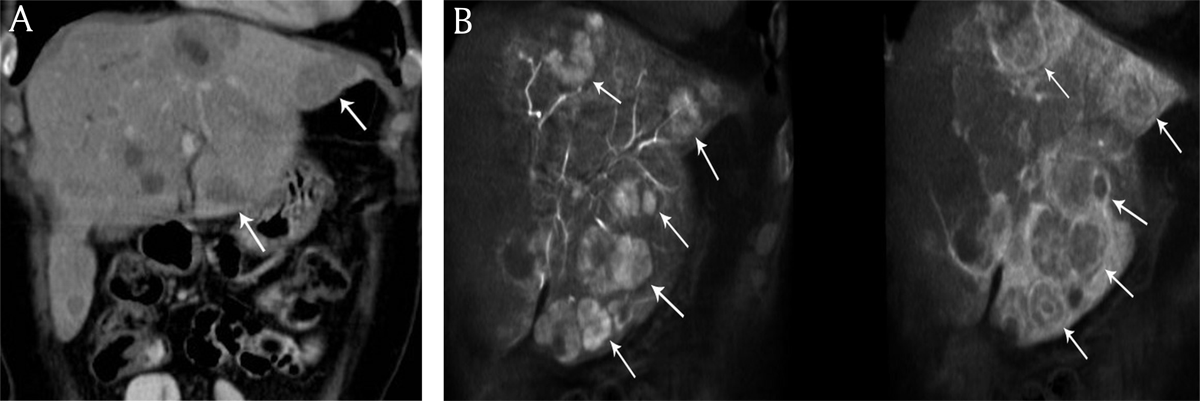

Figure 1

A) Coronal reconstructed contrast-enhanced computed tomography and B) cone beam computed tomography imaging in an 58-year-old woman presenting with bilobar neuroendocrine liver metastases. Increased number of liver metastases (white arrows) are identified on cone beam computed tomography imaging versus contrast-enhanced computed tomography.